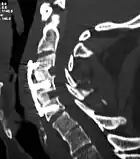

![]() X-rays of anterior cervical discectomy and fusion, C5C6 and C6C7. Lateral view. | |

The neurosurgeon or orthopedic surgeon enters the space between two discs through a small incision in front (= anterior) of and at the right or left side of the neck. The disc is completely removed, as well as arthritic bone spurs. The disc material, pressing on the spinal nerve or spinal cord, is then completely removed. The intervertebral foramen, the bone channel through which the spinal nerve runs, is then enlarged with a drill giving the nerve more room to exit the spinal canal.

To prevent the vertebrae from collapsing and to increase stability, the open space is often filled with a graft. That can be a bone graft, taken from the pelvis or cadaveric bone; or an artificial implant.[4] The slow process of the bone graft joining the vertebrae together is called "fusion". Sometimes a titanium plate is screwed on the vertebrae or screws are used between the vertebrae to increase stability during fusion, especially when there is more than one disc involved.